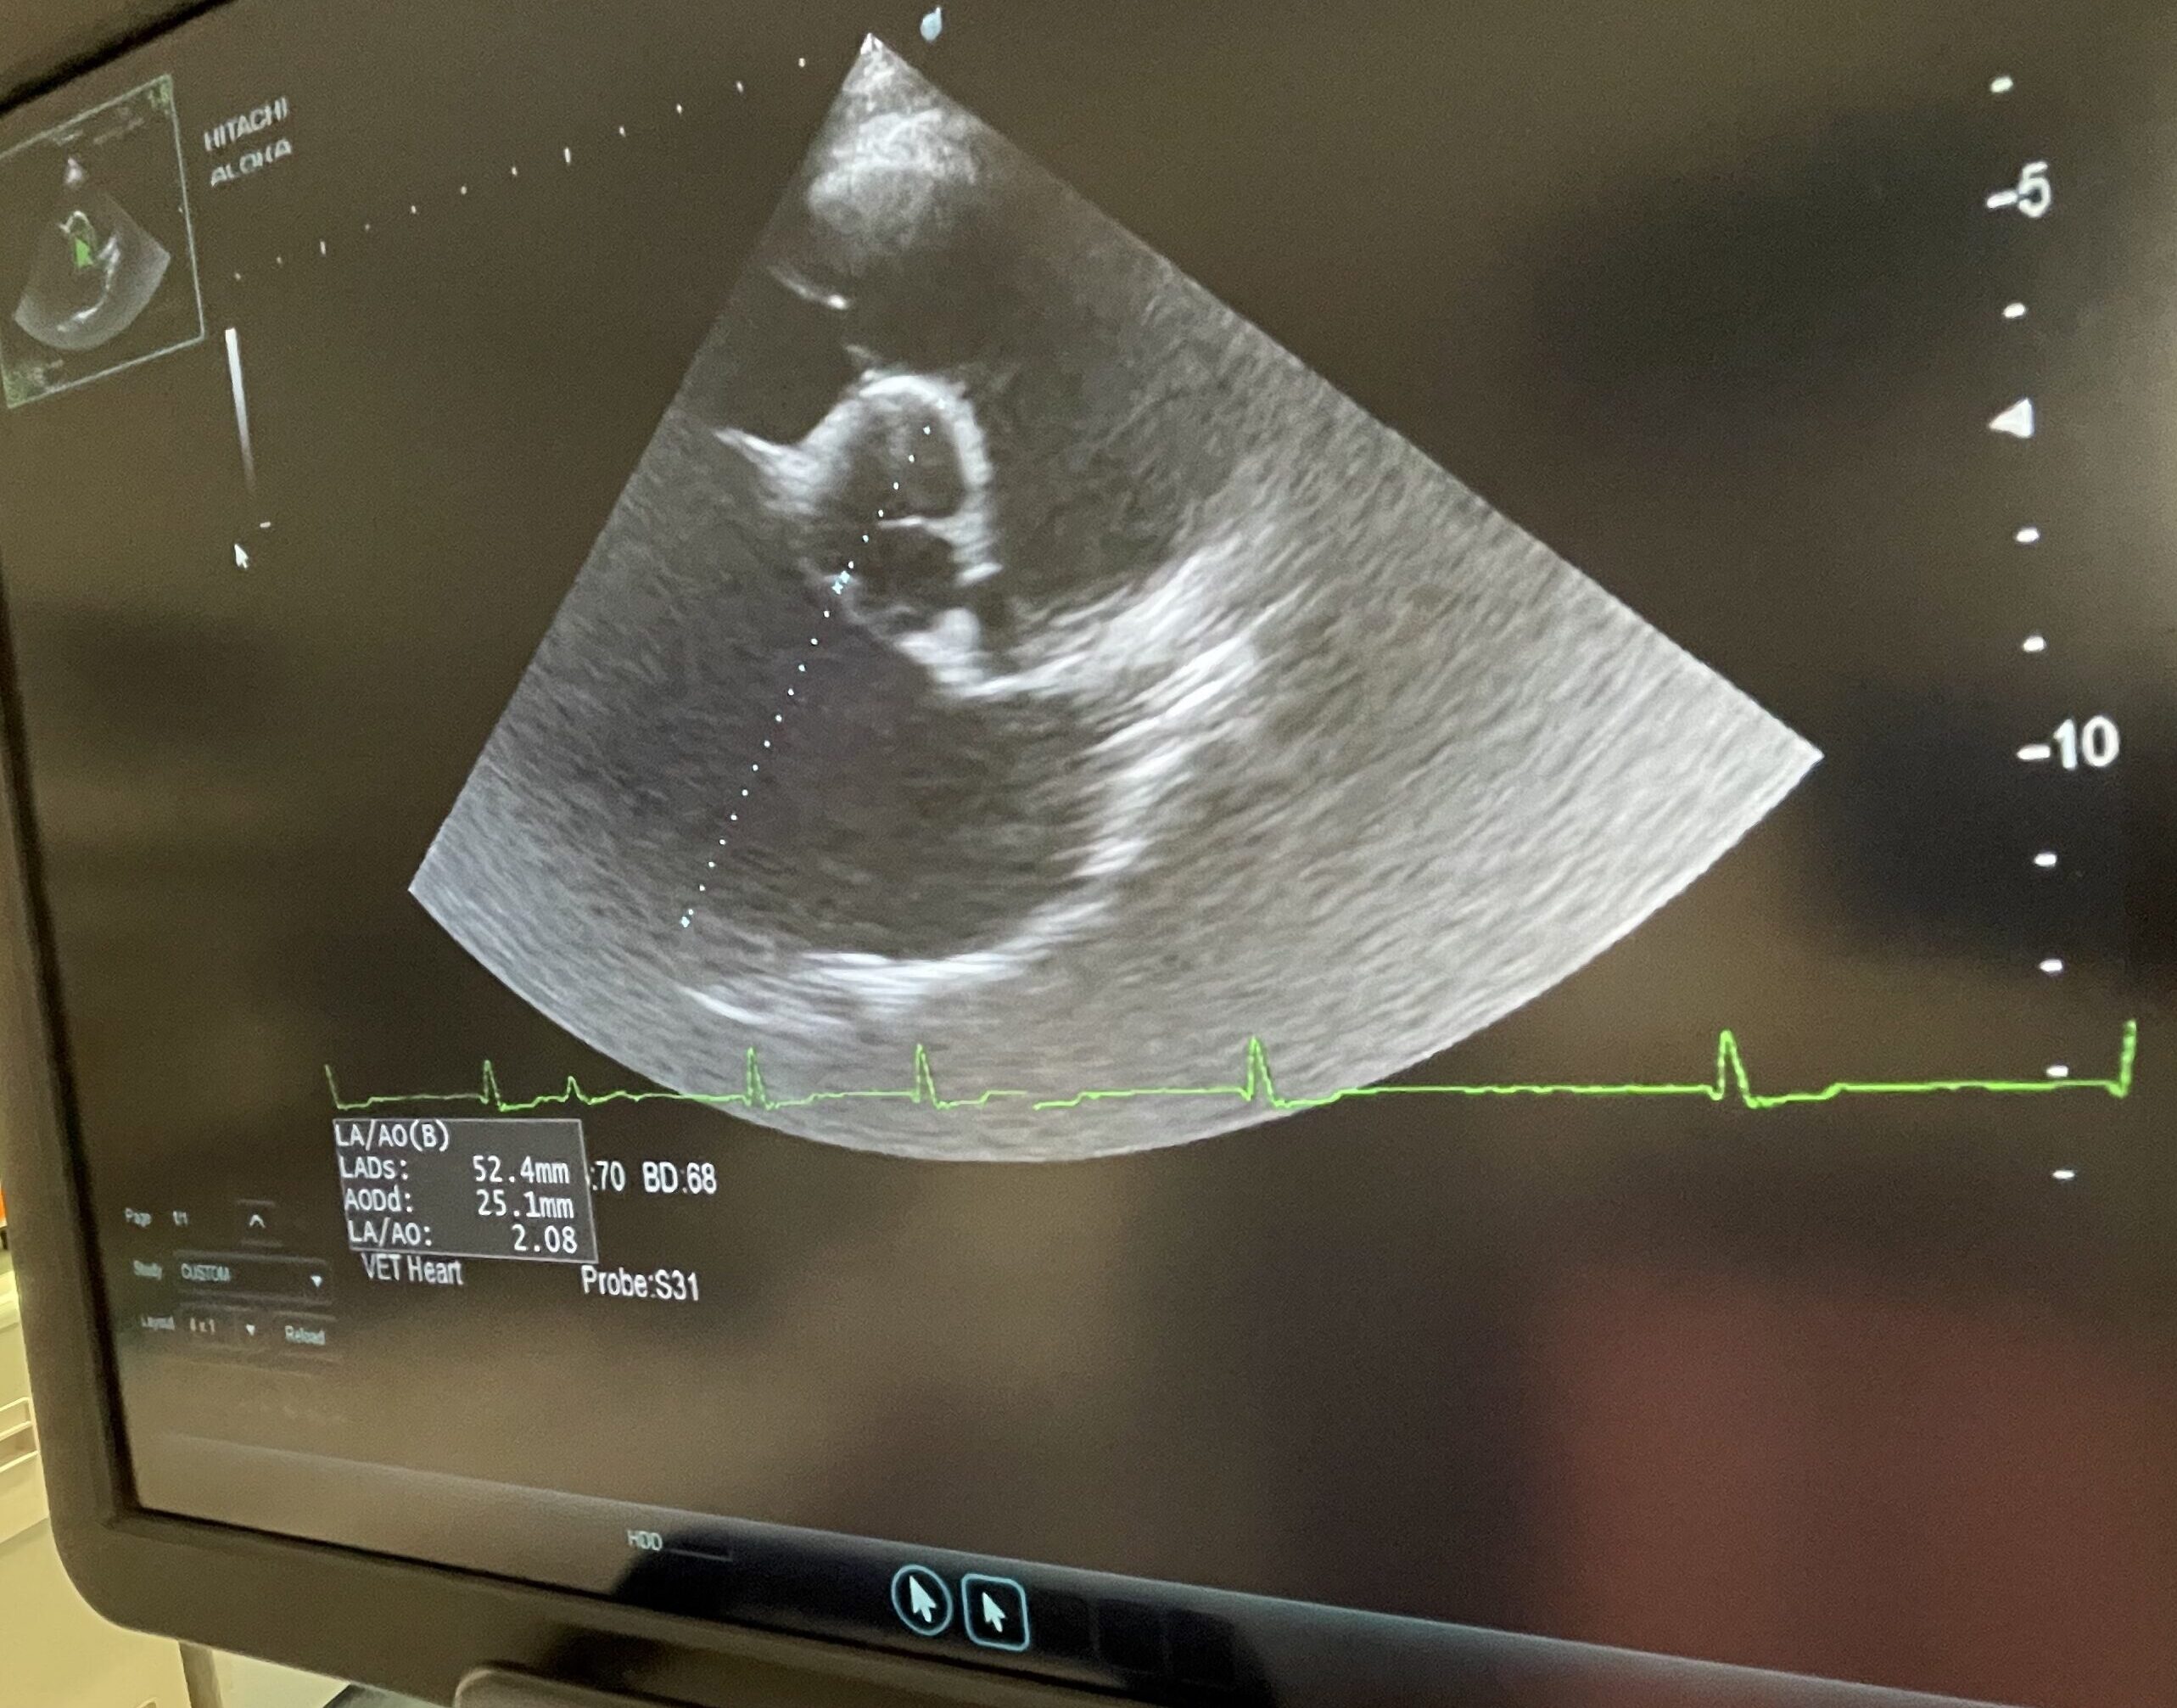

当院では循環器診療に力を入れており、

心エコー検査、レントゲン検査、内科治療管理まで行っています。

特に、安静時呼吸数の変化や軽度の心雑音など、

早期の段階での確定診断・評価と介入を大切にしています。